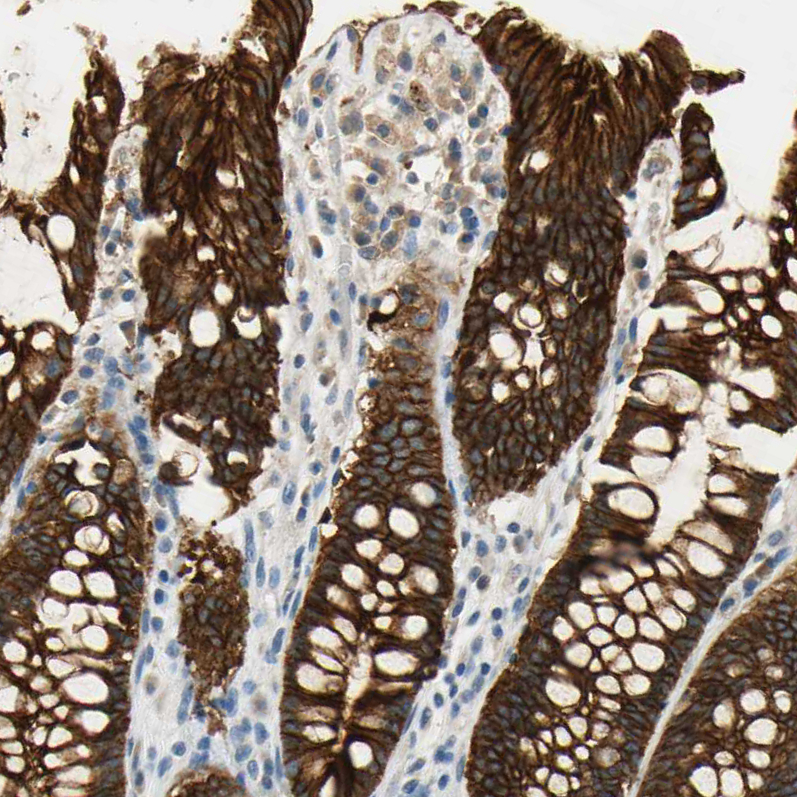

Immunohistochemistry analysis in human rectum and liver tissues using HPA004896 antibody. Corresponding DSG2 RNA-seq data are presented for the same tissues.